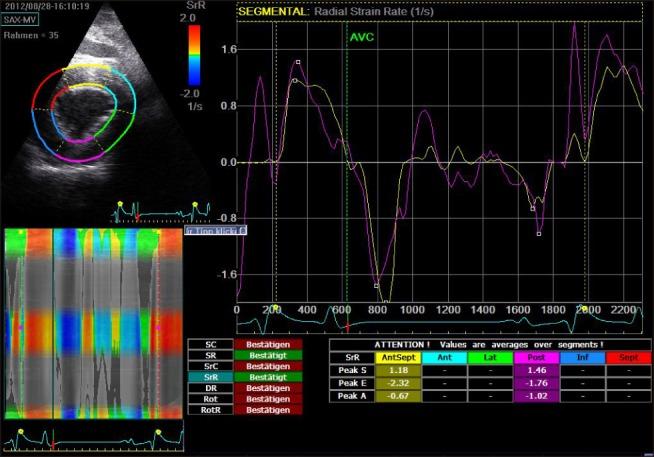

An effect of aging on cardiac morphology and function has been shown in humans. In horses, cardiac wall motion analysis using two-dimensional speckle tracking (2D-ST) has not yet been reported. Our study included 57 horses of different warmblood breeds between 3 and 30 years old. Age had a significant influence on left ventricular free wall (LVFW) systolic strain rate ( ≤ 0.05) and early diastolic relaxation ( ≤ 0.01). In the interventricular septum (IVS), systolic ( ≤ 0.01) and late diastolic ( ≤ 0.05) contraction velocities also increased with age. In our study, 2D-ST revealed important information on myocardial function, which was most evident in the LVFW, where measurements were highly reproducible. Aging seems to be associated with structural changes within the myocardium and with decreasing contraction capacity in old animals. These physiological, age-related processes should be considered when performing cardiac wall motion analysis of the 2D-ST results for the LVFW and IVS in horses.